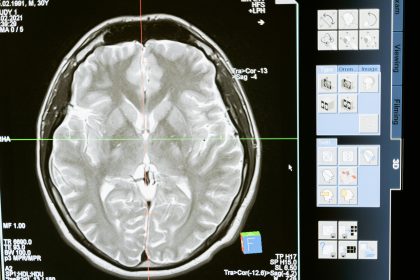

Comprehensive guide to brain injury treatment and rehabilitation — from emergency care to therapies, medications, technology, and long-term recovery.

Learn about moderate and severe traumatic brain injuries — their causes, symptoms, treatment, complications, and recovery outlook.